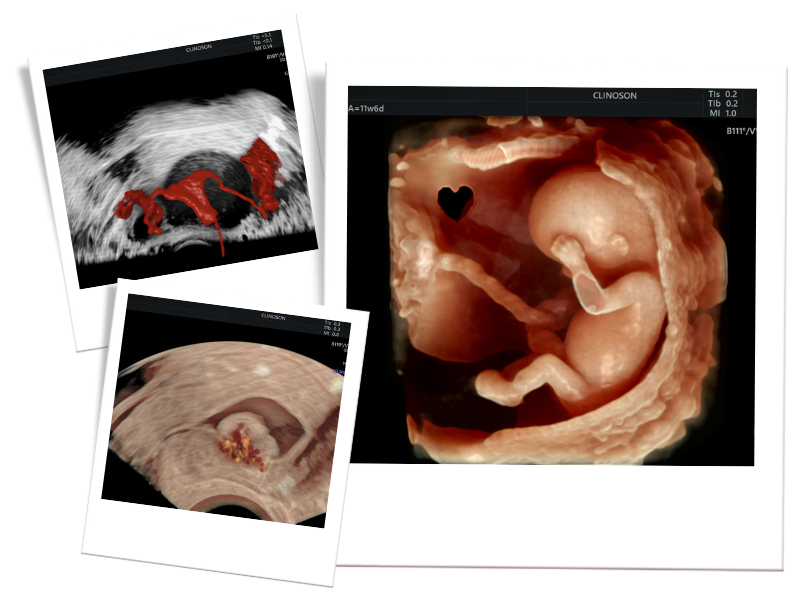

Sou médico ginecologista e obstetra com sólida formação acadêmica e atuação reconhecida em medicina fetal e exames diagnósticos de alta precisão. Desde o início da minha carreira, sempre acreditei que o verdadeiro cuidado à saúde da mulher exige mais do que conhecimento técnico: exige empatia, inovação e compromisso com resultados concretos.

Hoje, atuo ajudando mulheres a terem diagnósticos precisos e tratamentos modernos, incluindo o cuidado e diagnóstico de miomas uterinos, fertilidade e acompanhamento na medicina fetal.

Também, especializei-me em métodos como a ultrassonografia avançada para endometriose e o HyCoSy — um exame moderno e menos invasivo que traz conforto, precisão e segurança para mulheres que enfrentam dificuldades como infertilidade e dores pélvicas.

Meu compromisso com a saúde materno-fetal é oferecer um atendimento acolhedor, personalizado e baseado nas melhores tecnologias disponíveis.

- Título de área de atuação em Ultrassonografia em Ginecologia e Obstetrícia

- Título de área de atuação em Medicina fetal